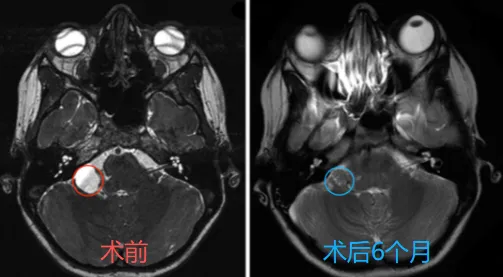

体格检查显示步态共济失调明显,左侧面部V2和V3分布区感觉明显...

这台手术由巴特朗菲教授主刀。虽然病灶周围紧邻面听神经、三...